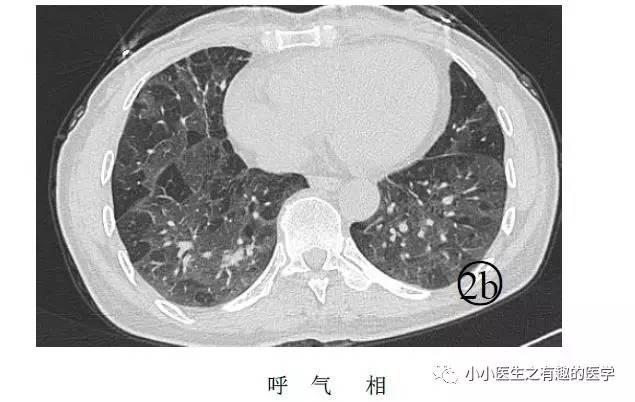

先来说说马赛克。

马赛克征象:由于气道疾病或肺血管性疾病,引起相邻的肺区血液灌注上的差别而出现的不均匀肺密度区,称马赛克灌注。

以图说话,下面都是马赛克,注意了。

假如CT平扫发现肺部某些地方血管稀疏,灌注不足,千万不要以为没事,有时候,就是肺栓塞,需要警惕。

马赛克,需要警惕肺栓塞,它是肺栓塞的间接表现。并且,在临床中,间断会遇到这样的情况。